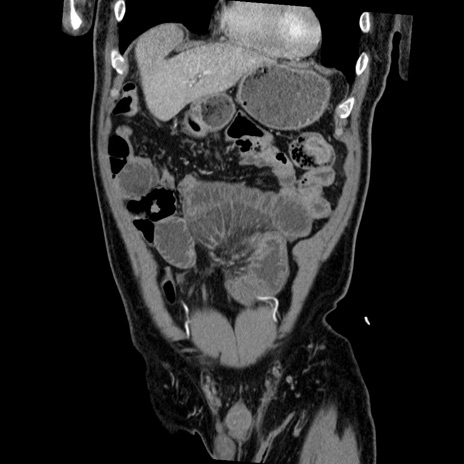

症例22(冠状断像)

【症例】50歳代男性

【主訴】腹痛

【現病歴】AVMからの被殻出血のため回復期リハ病棟入院中。 本日午後3時頃急に下腹部痛が出現した。

【既往歴】AVM、被殻出血、虫垂炎、高血圧

【身体所見】意識晴明、左半身不全麻痺、会話の理解は良好、36.5°C、腹部:膨隆、全体に板状硬、下腹部正中に圧痛点あり、反跳痛-、筋性防御不明、右下腹部にope scar

【データ】WBC 9400、CRP 0.06